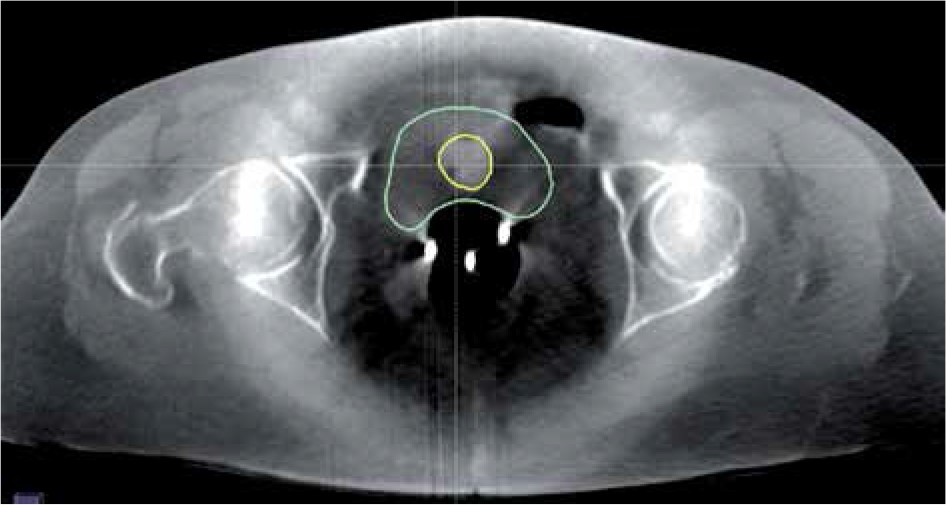

Modern BRT planning systems enable the visualization of doses on CT images by combining information of dose distribution with that of patient’s anatomy [18,19]. The quality of CT images is one of the key factors determining the complexity of dose distribution analysis in patient’s body. While CT images enable doses to be measured in most organ/regions during BRT, the quality of CBCT images reduces substantially the extent of those analyses [20]. Figure 5 shows a CBCT image made on an Acuity simulator for a volume treated with BRT. It displays the bladder (contoured with a green line), Foley’s catheter placed in the bladder (yellow line), and a three-channel Fletcher applicator (three bright points located centrally in the patient’s body). The quality of CBCT images makes it impossible to specify the exact location of the rectum and target volume and, thus, to perform a spatial analysis of doses deposited in those structures. It is, however, possible to analyze dose distribution in the bladder.